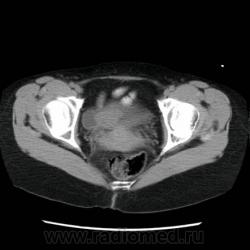

2. Похоже на новообразование мочевого пузыря, распространяющееся на устье мочеточника (это с моих скромных познаний в КТ)

Да, рак. Прооперировали в области в урологии.

Есть только три изображения. Что-бы "это" могло быть?